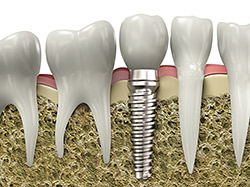

An implant is a synthetic tooth root in the shape of a post that is surgically placed into the jawbone. The “root” is usually made of titanium (the same material used in many replacement hips and knees), a metal that is well-suited to pairing with human bone. A replacement tooth is then fixed to the post. The tooth can be either permanently attached or removable. Permanent teeth are more stable and feel more like natural teeth.

The ideal candidate for implants is a non-smoker who has good oral health, including a sufficient amount of bone in the jaw, and healthy gums with no sign of gum disease.